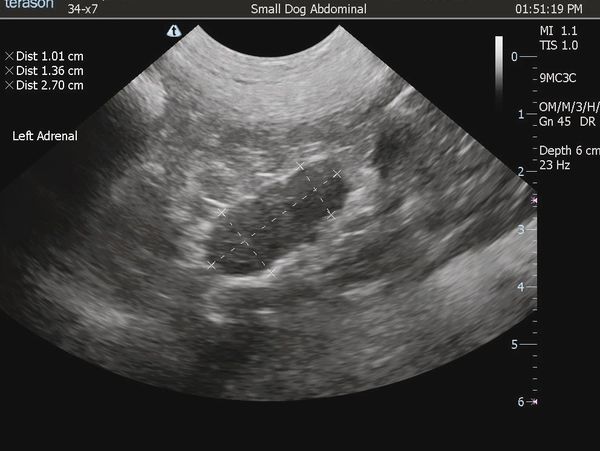

We provide comprehensive abdominal ultrasounds to thoroughly evaluate all major organs and structures. Every scan includes expert interpretation by board-certified veterinary internist Dr. Larson (Music City Pet Internal Medicine Solutions).

An ultrasound-guided fine needle aspirate (FNA) can be added prior to the appointment for targeted sampling—just ask for details.

We perform full Doppler echocardiograms on every heart case, ensuring a detailed look at cardiac function and structure. Each study is guided in real time by an Oncura professional sonographer for top-quality results, and every scan is interpreted by a board-certified Oncura cardiologist for accurate, actionable insights.